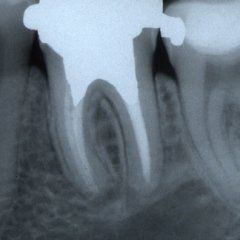

Il trattamento endodontico

P3: Il trattamento endodontico si rende necessario quando la polpa del dente, comunemente chiamata dai Pazienti “nervo” è stata irrimediabilmente danneggiata da carie penetranti, fratture dentali, traumi o da cause imputabili a pratiche odontoiatriche scorrette. A volte la devitalizzazione del dente si rende necessaria, in corso di riabilitazioni protesiche complesse, per prevenire possibili problemi di ipersensibilità o per poter coinvolgere nel progetto terapeutico di recupero denti già di per se compromessi dal punto di vista parodontale. Presupposto per ottenere il successo in tale terapia è l’applicazione di un serio protocollo operativo che prevede tra l’altro l’uso di un telo di lattice, chiamato comunemente “diga”, che consenta la detersione e la pulizia dei canali del dente in un ambiente sterile e il controllo delle diverse fasi del trattamento attraverso delle radiografie endorali.